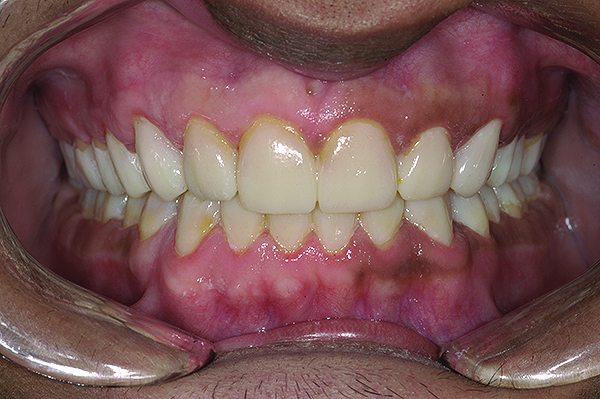

Figure 2. Preoperative 1:2 retracted frontal view.

Figure 2